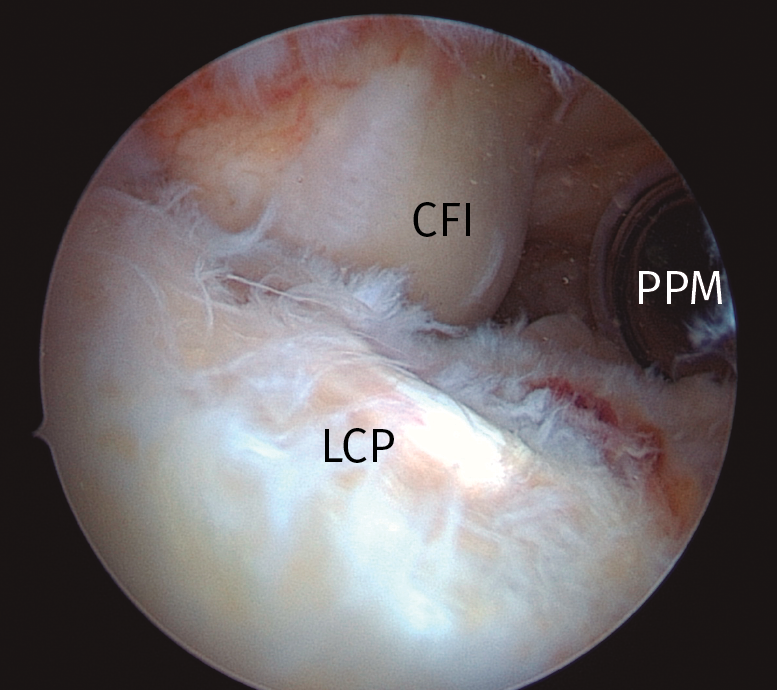

Figura 1. Imagen del compartimento posteromedial desde una visión transescotadura desde el portal anterolateral, rodilla derecha. Se evidencia la presencia de un cuerpo libre “oculto”. CFI: cóndilo femoral interno; CL: cuerpo libre; RPMI: rampa posterior de menisco interno.

La exploración transescotadura de los compartimentos posteriores puede cambiar el diagnóstico en el 18% de los casos de artroscopia de rodilla y alterar el plan terapéutico en el 11%; en casos de cirugía del LCA puede ser incluso mayor(29). Puede ayudar a diagnosticar un 45% de roturas meniscales ocultas, y un 33-36% de cuerpos libres ocultos(28,29).